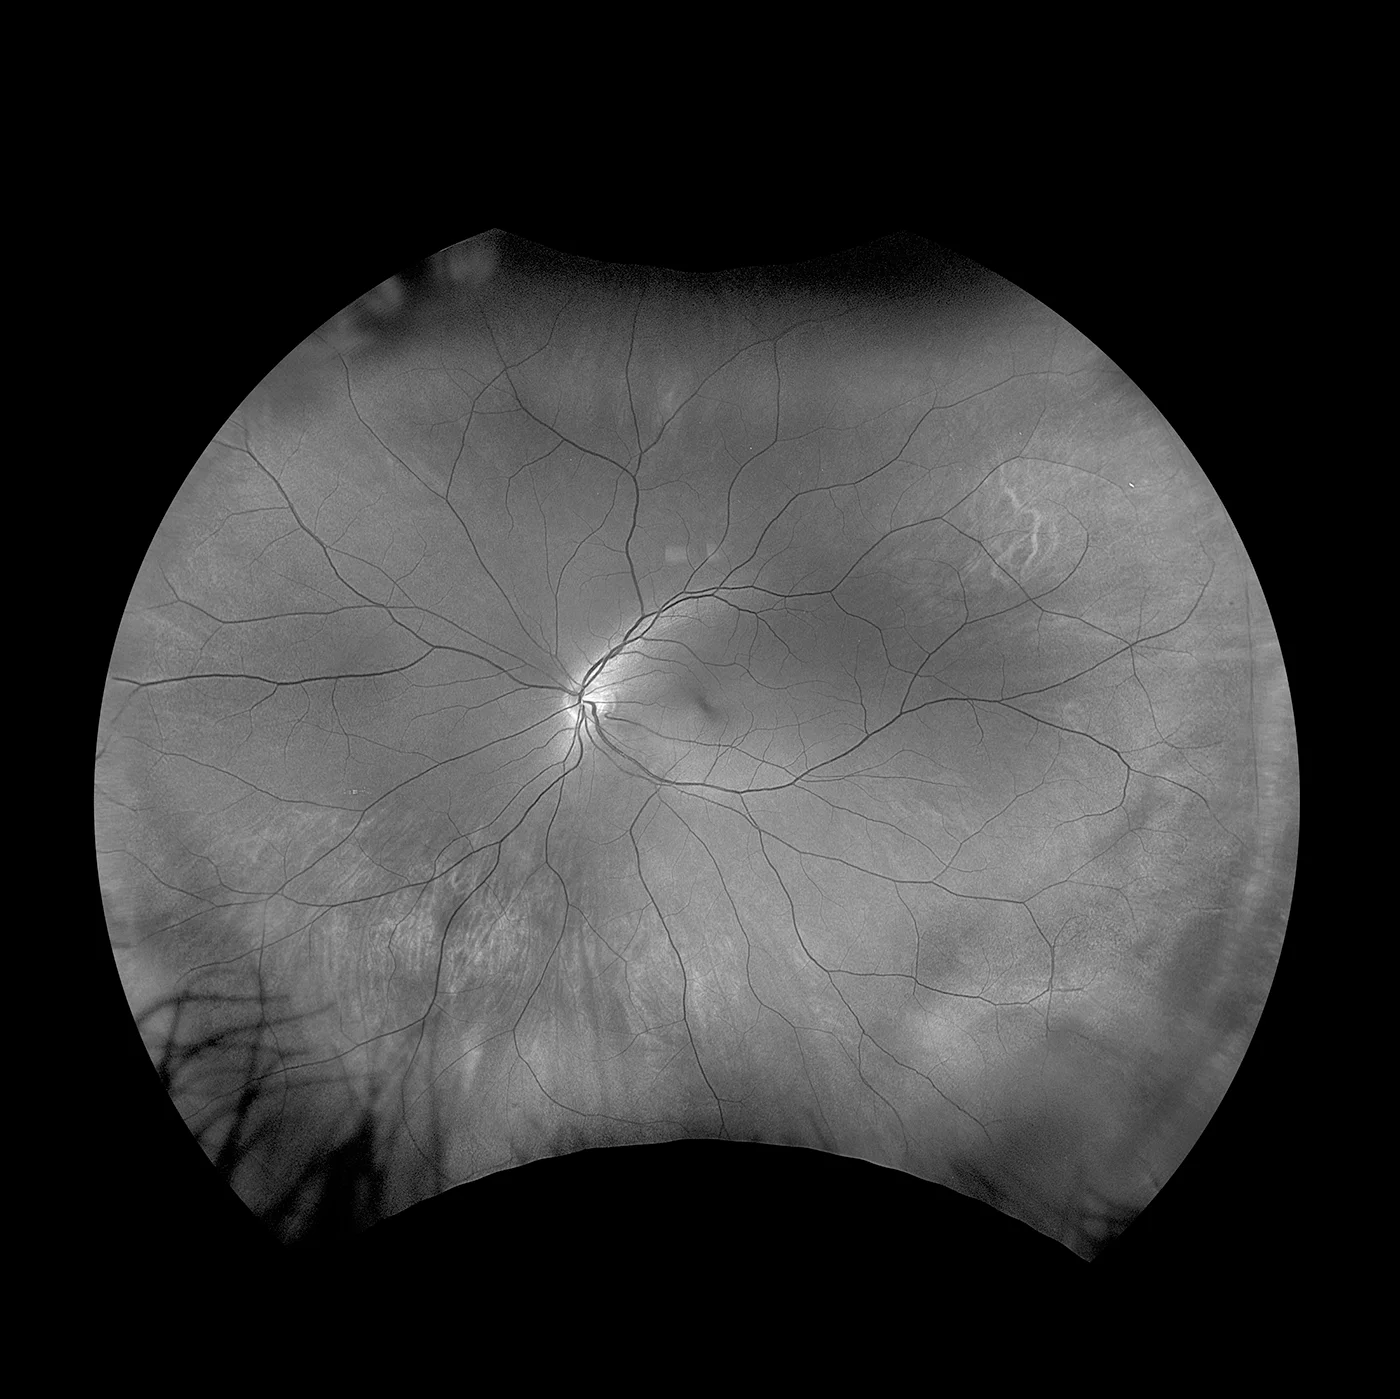

MonacoPro bietet Ihnen faszinierende neue Möglichkeiten, Ihre klinischen Untersuchungen zu vervollkommnen. Als einzige Ultra-Weitwinkel- Bildgebung der Netzhaut mit integriertem SD-OCT liefert Ihnen MonacoPro ein 200° optomap-Bild in weniger als ½ Sekunde und erstellt zudem 40°-OCT-Querschnittsaufnahmen von Netzhautstrukturen. MonacoPro ermöglicht eine schnelle multimodale Bilderfassung mit Farb-, Autofluoreszenz- und OCT-Scans für beide Augen in nur zwei Minuten.

optomap farbe rg und optomap plus (Rot und Grün Laser): |